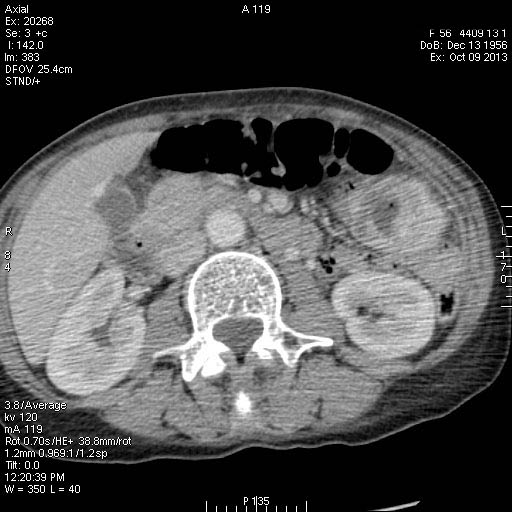

Женщина средних лет поступила в хирургическое отделение с кишечным кровотечением.

Пальпируется образование в мезогастриуме слева. При УЗИ определяется тумор, не связанный с толстой кишкой.

КТ

Операция - обнаружена опухоль тонкой кишки, предположительно гемангиома, выполнена резекция части кишки.

Гистологический ответ - GIST.

GIST тонкой кишки